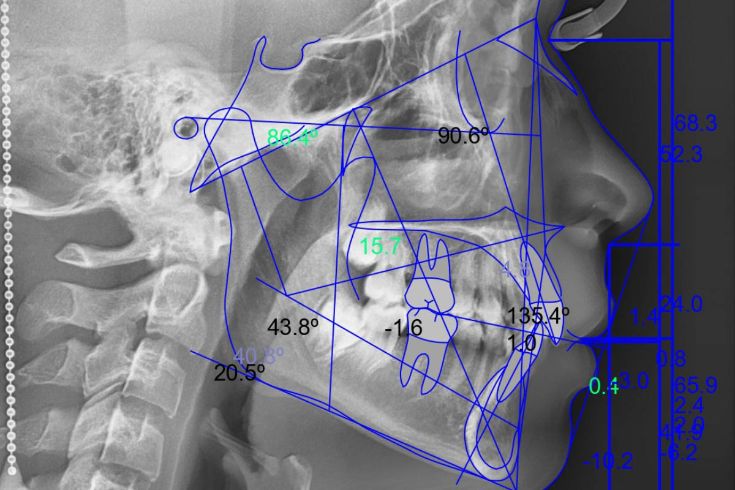

Análisis Cefalométrico

El análisis cefalométrico permite medir y analizar las estructuras óseas del cráneo. Ofrece datos precisos sobre la relación entre los dientes, maxilares y la base del cráneo, esencial para definir planes de tratamiento.